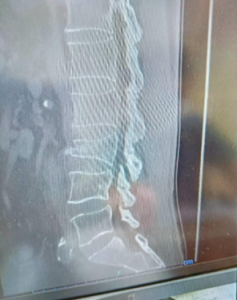

● 3月17日(整形外科・CT)

• ここで初めて「腰椎3番の圧迫骨折」確定診断

● 6月16日(整形外科)

• 圧迫骨折の治癒を確認